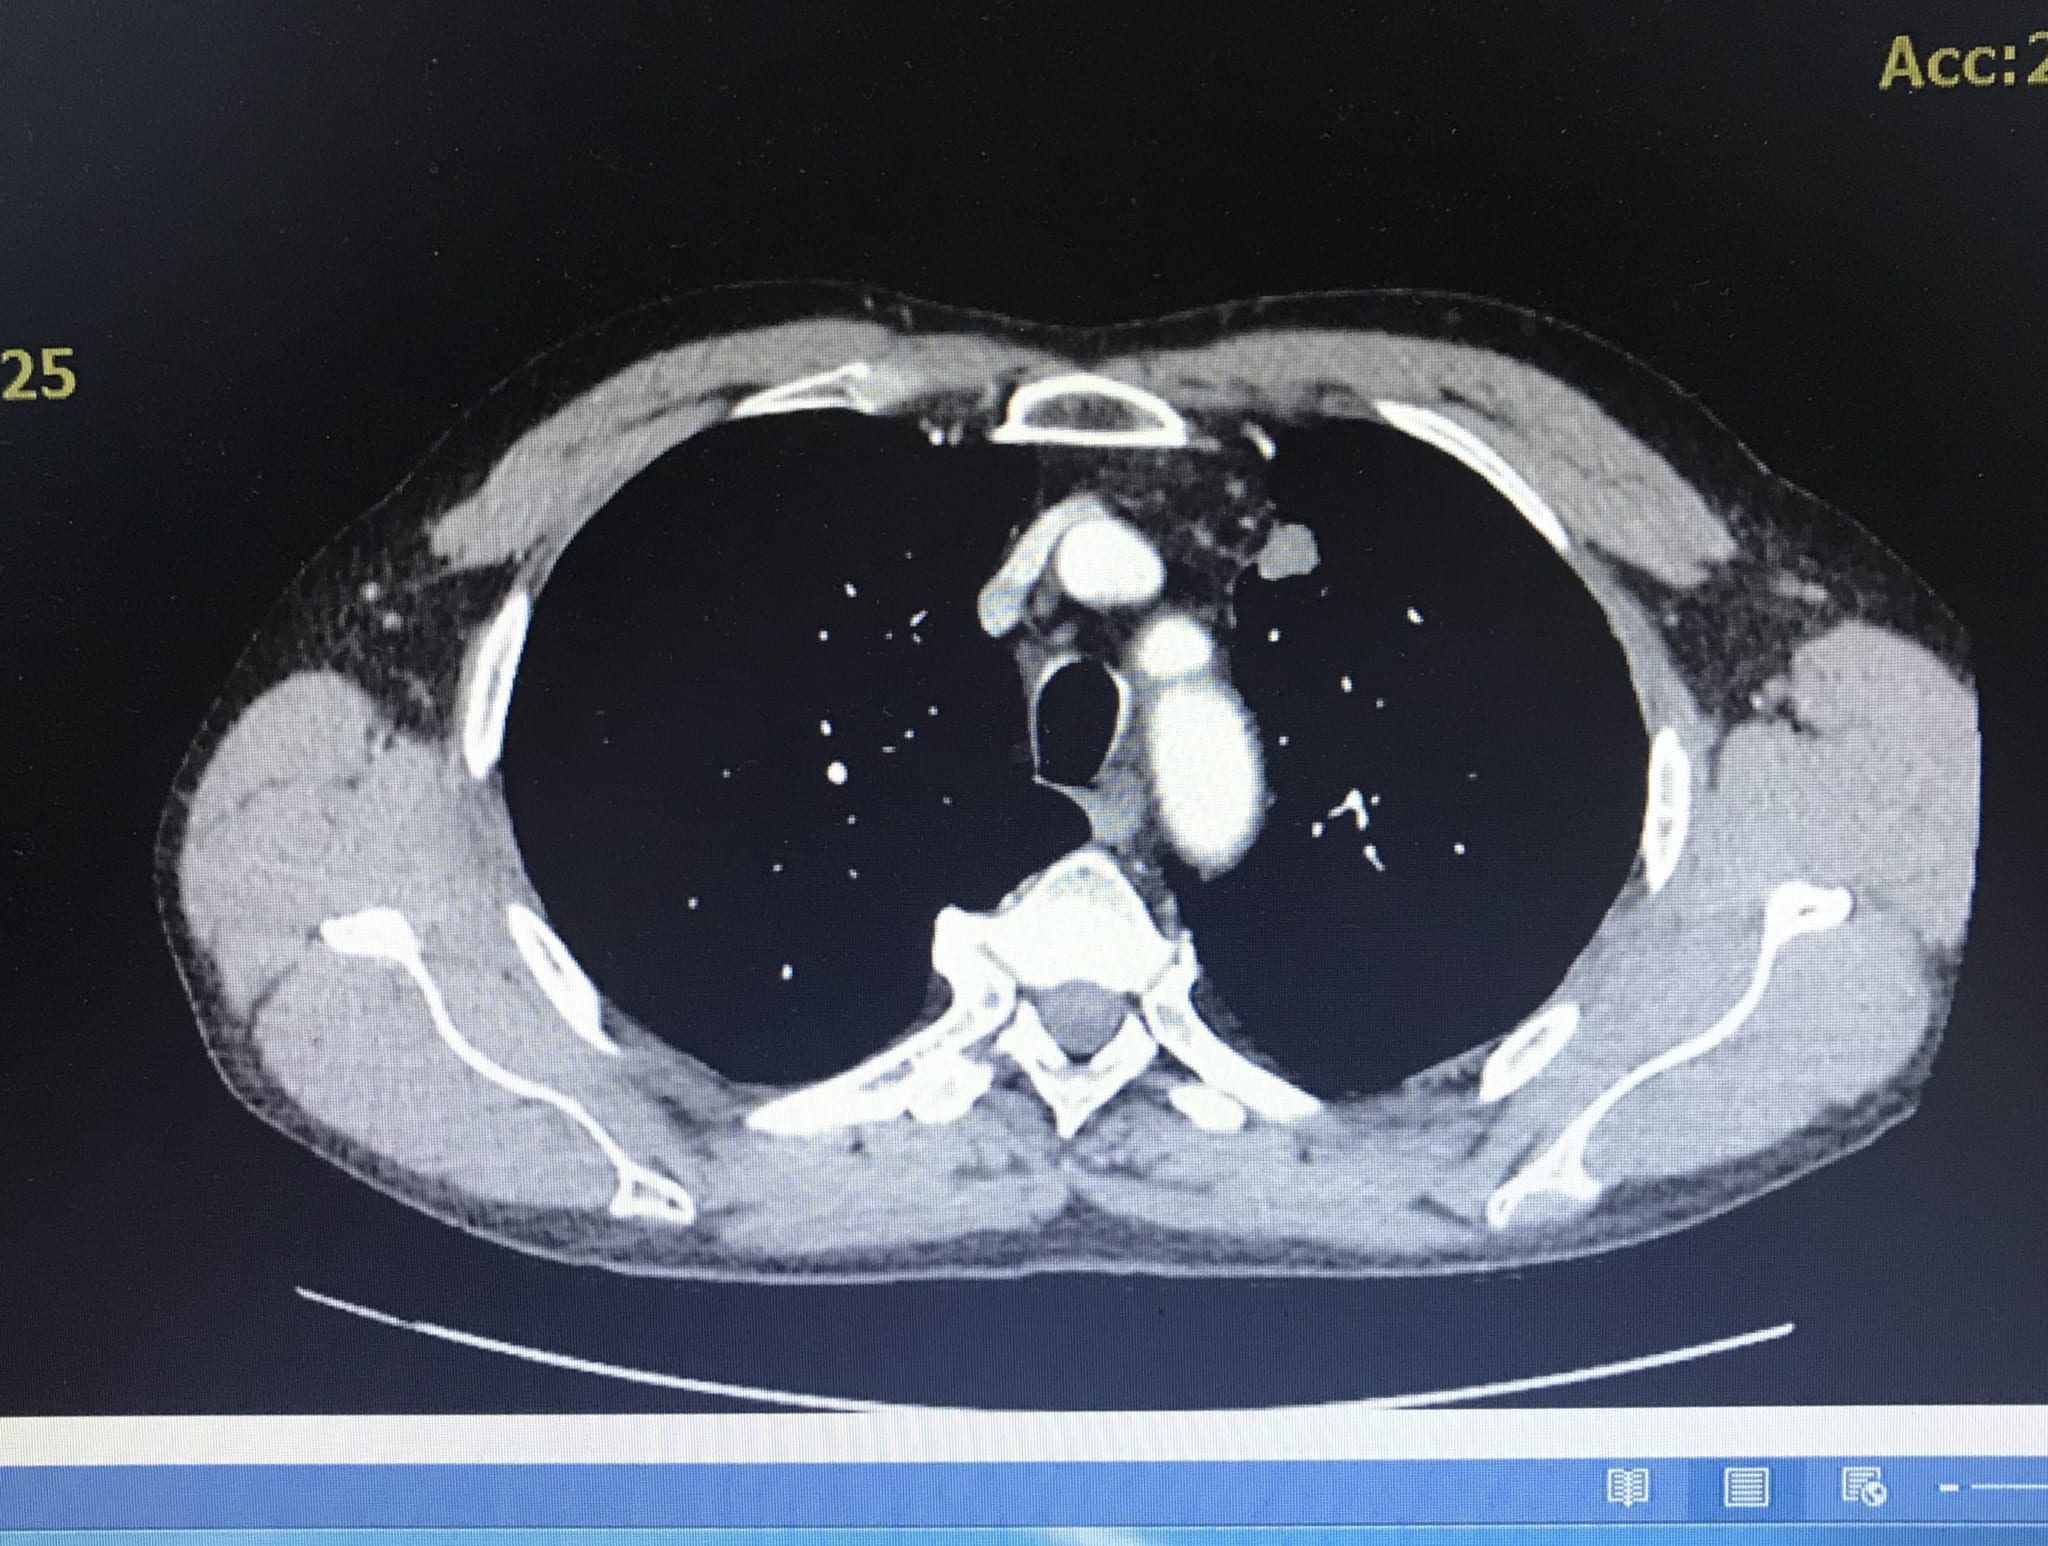

Bệnh nhân được hẹn về nhà theo dõi nhưng khi người bệnh đau tức ngực hai bên, ho đờm vàng nên được gia đình đưa đến khám tại Bệnh viện đa khoa Quốc tế Hải Phòng. Qua thăm khám và chụp CT ngực cho thấy, bệnh nhân có u thùy trên phổi kích thước 2,5×1,7cm.

Với mong muốn xác định khối bất thường ở phổi là lành tính hay ác tính để tìm ra hướng điều trị tốt nhất, chấm dứt tình trạng khó chịu kéo dài cho bệnh nhân. Các bác sĩ Khoa Nội, Bệnh viện đa khoa Quốc tế Hải Phòng đã tiến hành hội chẩn kĩ lưỡng và quyết định thực hiện kỹ thuật sinh thiết phổi. Ths.BSNT Phạm Đắc Thế – Phó Khoa Nội, Bệnh viện đa khoa Quốc tế Hải Phòng đã thực hiện thành công kỹ thuật này. Kết quả mô bệnh học của sinh thiết phổi người bệnh bị ung thư biểu mô tuyến xâm nhập.